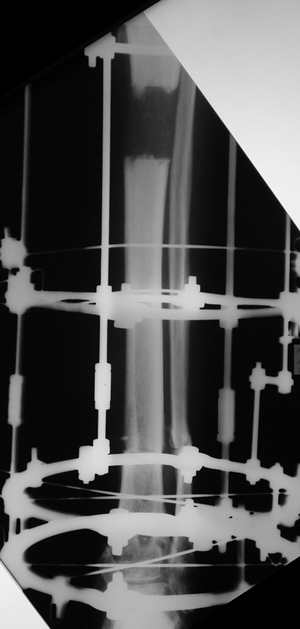

Мужчина, 33 года, резекция б\б кости по поводу остеомиелита после открытого перелома. Стандартная методика билокального остеосинтеза (рис 1 и 2). В конце удлинения выявилось неудовлетворительное взиморасположение перемещенного фрагмента и дистального отломка (рис 3). Планирование (рис 4).

Адаптация отломков гексаподом за 5 дней (рис 5). Замена гексапода на обычные штанги (рис 6 и 7)